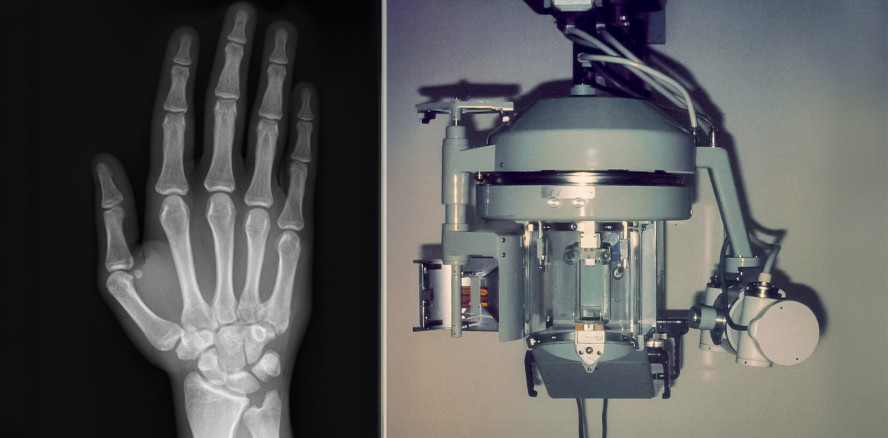

Der Begriff der Zeitenwende wird oftmals überstrapaziert. In Bezug auf bildgebende Verfahren in der Zahnmedizin scheint er gerechtfertigt: es ist eine klare Entwicklung hin zu neuen Verfahren zu beobachten, vor allem solchen, die ohne Röntgenstrahlung auskommen. Der vorliegende Beitrag ist der erste Teil einer zweiteiligen Darstellung.

Die zahnärztliche Radiologie verdient deutlich mehr Aufmerksamkeit als ihr gemeinhin zuteilwird – entscheidet doch die Qualität der Aufnahme...

Die zahnärztliche Radiologie verdient deutlich mehr Aufmerksamkeit als ihr gemeinhin zuteilwird...